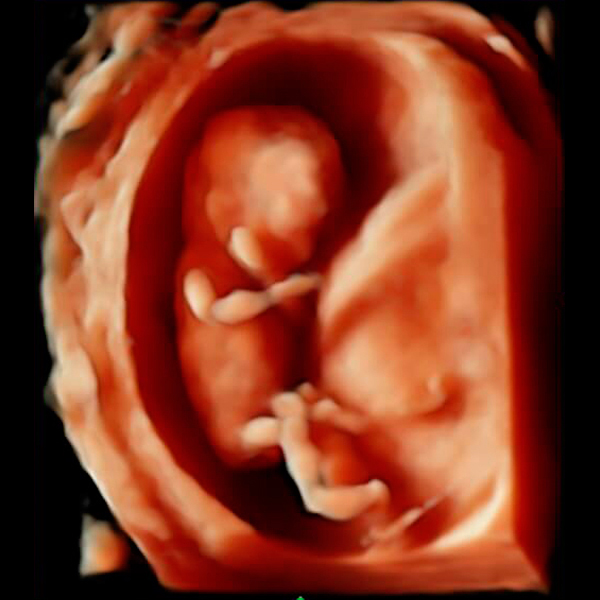

Actualmente realiza un Doctorado Internacional en Medicina Fetal avalado por las universidades de KU Leuven (Bélgica), Universidad de Barcelona (España) y la Universidad de Lund en Suecia, tres instituciones líder en el segmento de la medicina fetal a nivel mundial.